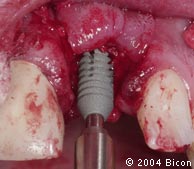

67. | 用直柄上的定制就位夹具使就位力沿种植体内径和基台柱的长轴传递,以便于形成锥形锁柱的连接关系。 |

![]() |

68. | 一体化基台冠的镜观。 |